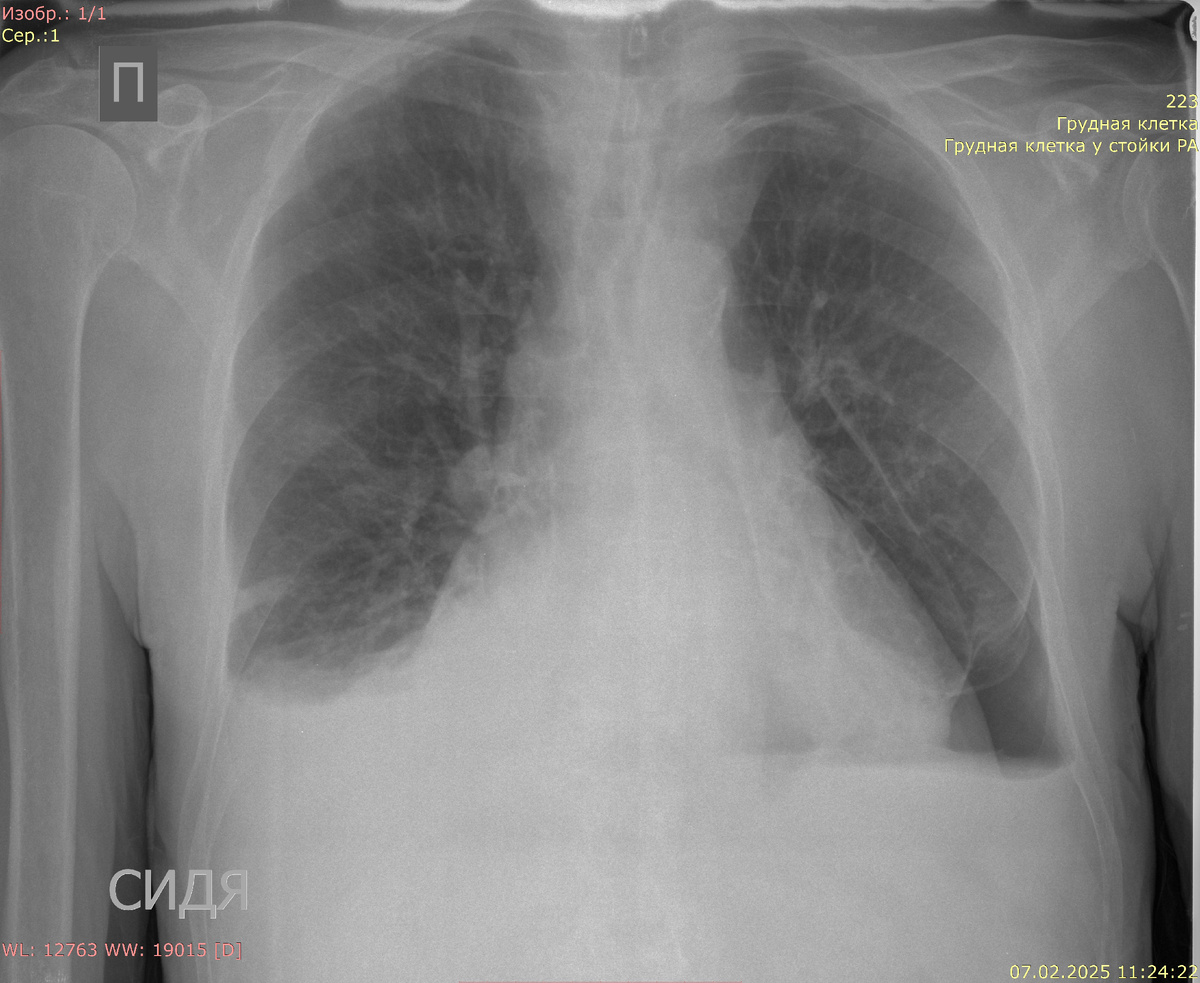

После лечения (плевральная пункция)

Рентгенография органов грудной клетки в прямой проекции:

Видимые дыхательные пути проходимы. Тень средостения не смещена, расширена. Корни легких четкие, структурные, не расширены. Очаговых и инфильтративных изменений в легких нет. Двусторонний минимальный (на уровне синусов) плевральный выпот. Слева в нижнем легочном поле аваскулярная зона до 35 мм. Костно-деструктивных изменений нет.

Заключение: двусторонний минимальный плевральный выпот. Пневмоторакс слева.